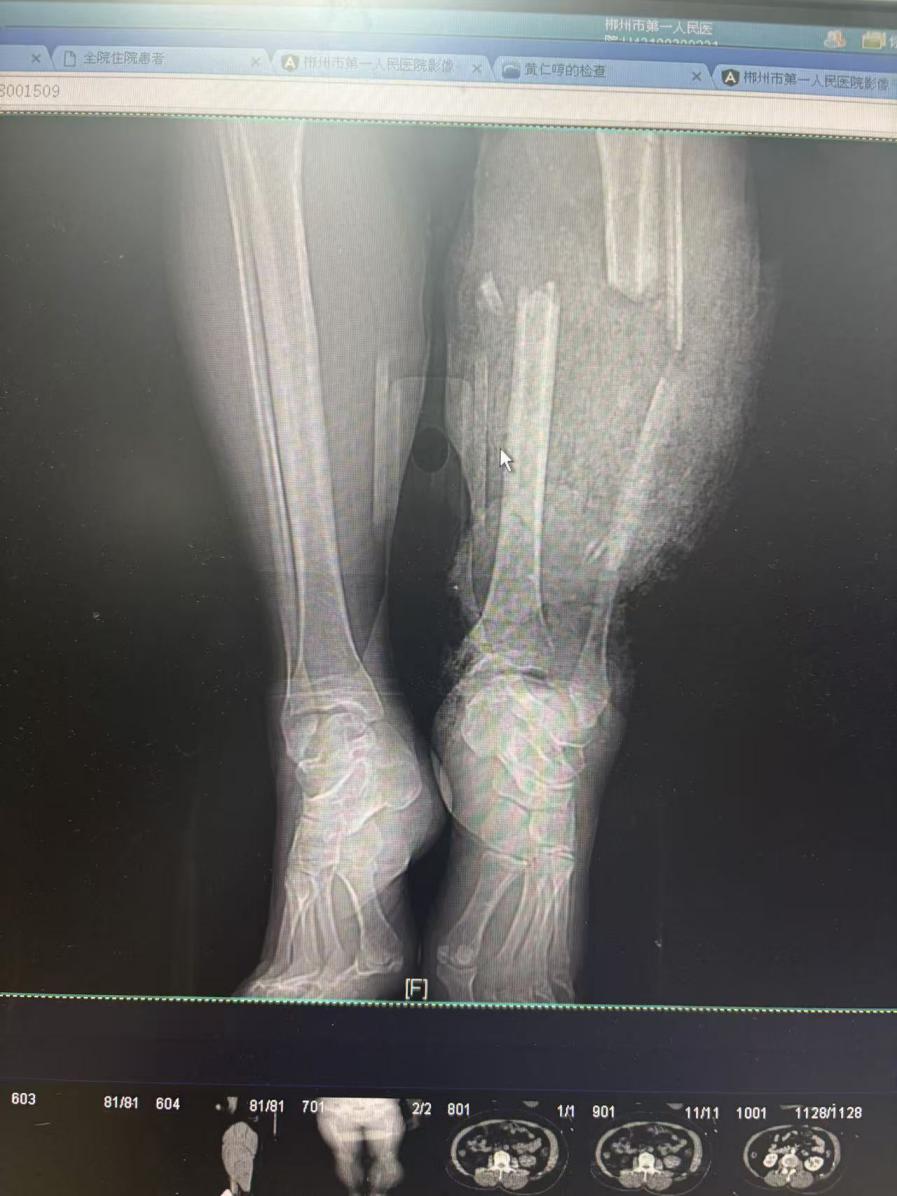

大众卫生报·新湖南客户端1月29日讯(通讯员 唐静霞)1月28日下午6时许,宜章一名40多岁女性因遭遇车祸,左腿下肢严重毁损,皮肤完全撕脱、胫腓骨多处呈现粉碎性骨折,下肢血管、肌腱断裂多处,当地医院于8时50分,将患者紧急送至郴州市第一人民医院急诊科,由于伤情十分严重,患者此时已呈失血性休克状态。

影像检查明确伤情后,患者从ICU转入手术室。麻醉团队在患者循环不稳定的情况下,迅速完成麻醉诱导与生命支持;手足显微外科何雨生主任带领曾冬莲副主任医师、陈贝博士手足显微外科团队积极响应,精准施策,争分夺秒处理血管损伤、精细吻合重建血供以争取保肢,同时有序处置毁损的骨骼与软组织。团队分工明确、协同作战,争分夺秒地为患者完成了紧急清创、骨折固定、血管移植等一系列关键抢救手术。

(患者经过抢救保肢成功)